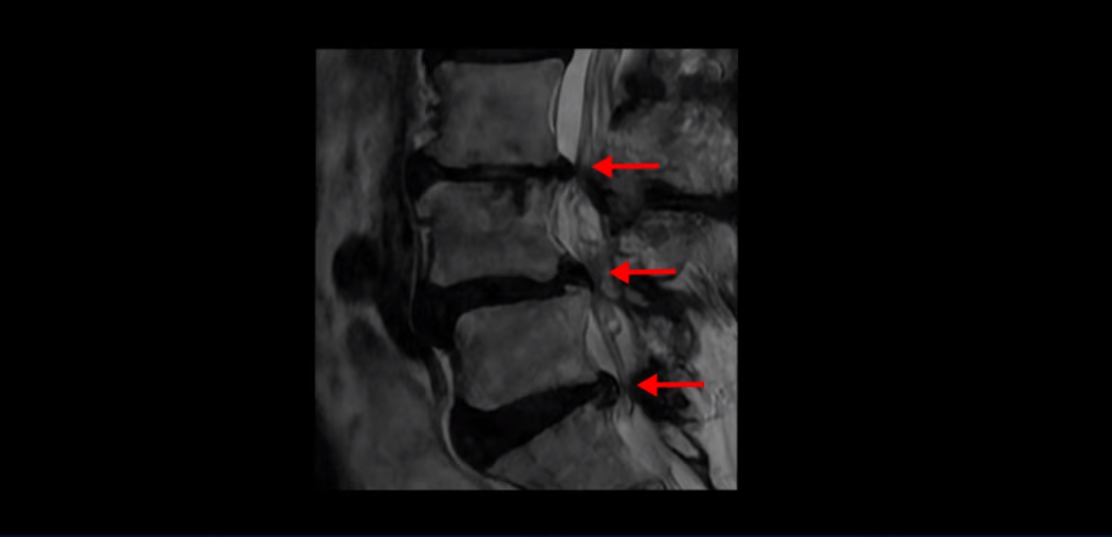

제가 먼저 이분 MRI를 보고 설명해 드린 후 어떻게 이런 분들을 수술 없이 허리 기능재활치료로 호전시킬 수 있는지 자세히 설명드리겠습니다. 이분 허리가 보시다시피 여러 마디가 퇴행되어 있고

4번 5번에는 뼈가 밀려 나간 전방전위증도 있습니다.

4번 5번 마디를 자세히 보면 심한 중심성 협착이 있어서 신경 구멍이 매우 좁아져 있습니다.

또 신경 가지가 빠져나가는 추간공도 매우 좁아져 있습니다.